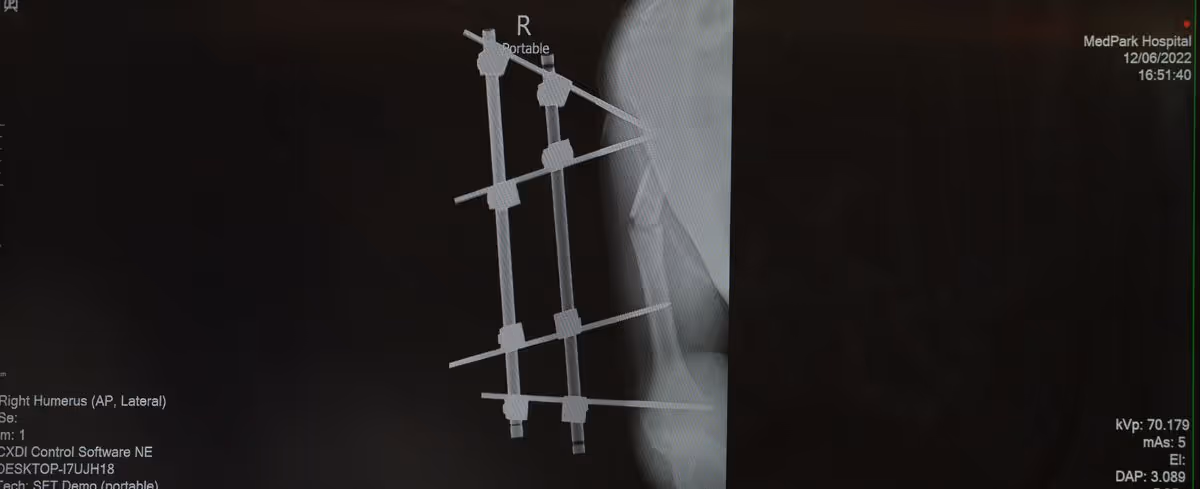

His friend who witnessed the incident said he saw Ryan suddenly hunch over the motorbike falling asleep before crashing into a barrier. His face and body were bloody. The wounds are significant, especially the ones above the right ribs. A first responder team arrived and rushed him to a hospital. X-rays revealed fractures of his right clavicle and arm in four places. The doctor performed preliminary external arm bone fixation.

“He had four fractures, one of the right clavicle, treated at the first hospital with open reduction and internal fixation. The other three were on his right arm, treated with an external fixator frame. In addition, he had a palm-length wound over his ribs. He could not flex his right wrist back, probably due to nerve damage in his right arm. Plus, he had intracerebral hemorrhage. The injuries spread throughout his entire body.”

In the past, external fixation was usual because of its convenience and simplicity -- small metal pins are inserted through the skin and drilled into the bone fragments above and below the fracture site. An external frame may hinder sleep and movement of the affected arm. In Ryan's case, the referring hospital performed external fixation as a stop-gap measure; it is not as strong as internal fixation. Another disadvantage is the possibility of nonunion. Because of this, Dr. Pongsakorn decided to reoperate for fracture repair.